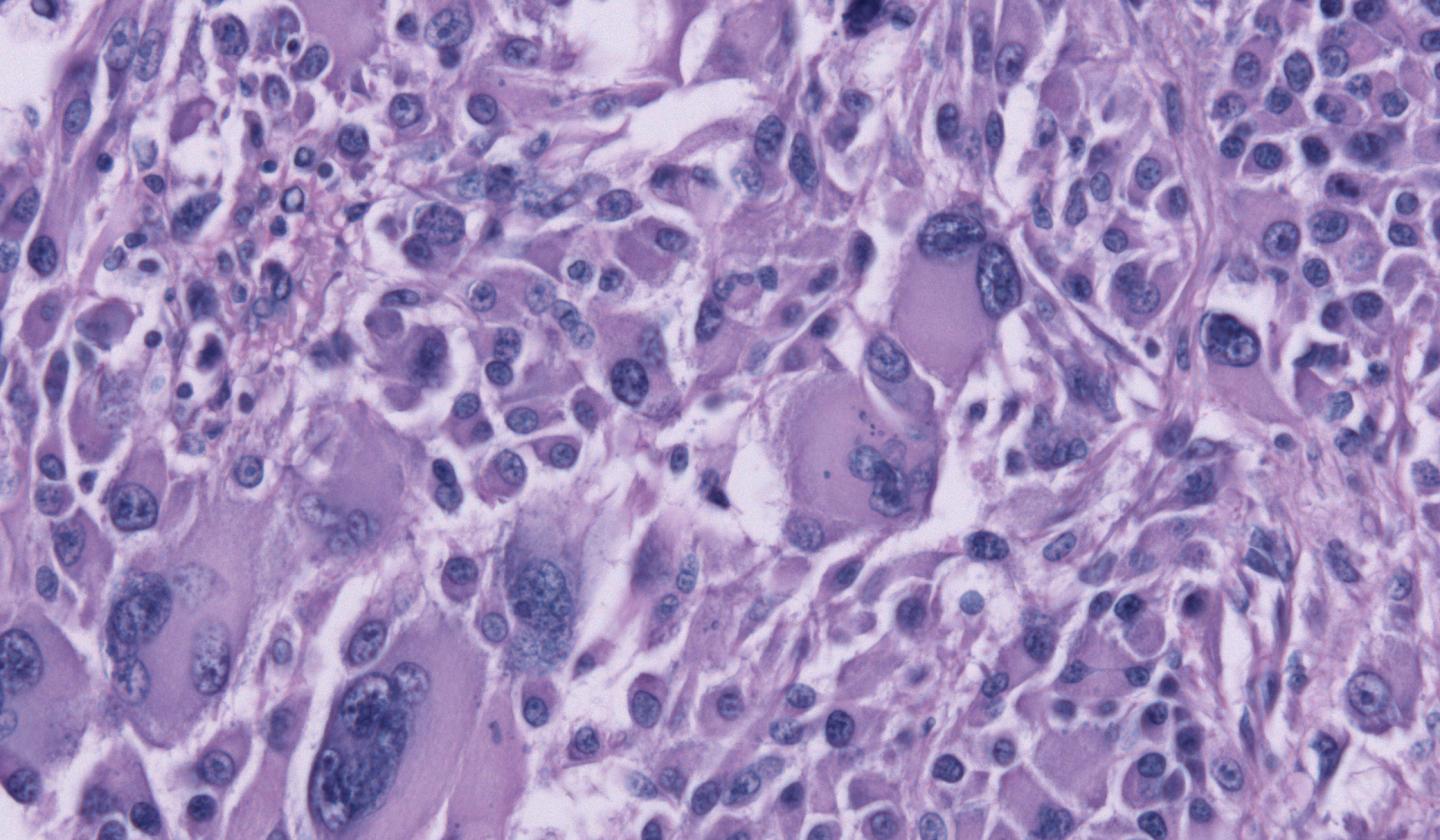

The scientists' goal is to eradicate glioblastomas, particularly nasty cancerous tumors found in the brain. From the time of diagnosis, the average patient has a year to live. With the current standard of treatment - including surgery, chemotherapy, and radiation - a patient might live an extra two months beyond that.

One of the major problems with treating glioblastomas is that it's nearly impossible to surgically remove every cancerous cell.

"These cells hide away in little niches in the brain," said Robert Gourdie, another grant recipient and the director of the Center for Heart and Regenerative Medicine Research at the Virginia Tech Carilion Research Institute. "You think you've resected the tumor and killed the disease off, and then it springs up somewhere else like whack-a-mole."

The obvious answer is to douse the remaining cells with chemotherapy drugs, but glioblastomas are resistant to all but one. The only effective drug available to treat this type of cancer is temozolomide, known as TMZ. Therein lies the other major problem. Glioblastomas make it a point to know their enemy, and the cells quickly become resistant to TMZ as well.